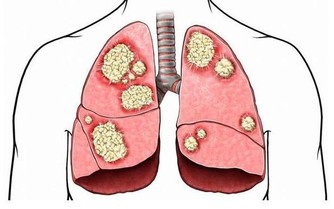

前列腺可以說是男人的“生命腺”,一旦出現問題,嚴重影響男性的身心健康,

而前列腺炎是常見的男科疾病之一,發病率高,應引起高度重視。

前列腺炎,除了一般的細菌感染外,生活中的很多壞習慣也會增加罹患前列腺炎的機率。